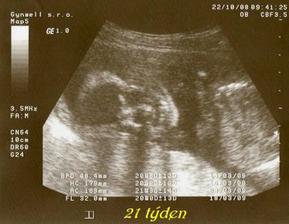

tak tohle album obsahuje vše co se týká našeho prvního miminka, které nosím pod svým srdíčkem, výbavičky co chystáme a co bychom chtěly nachystat.. Narodit se má 6.3.2009 , nevíme co to bude - asi necháme jako překvapení.